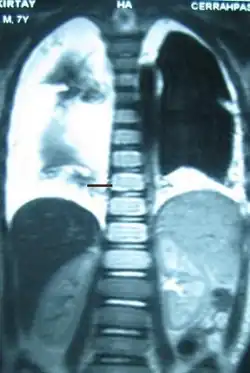

Chest X-rays can detect a chylothorax. It appears as a dense, homogeneous area that obscures the costophrenic and cardiophrenic angles. Ultrasounds can also detect a chylothorax, which appears as an echoic region that is isodense with no septation or loculation. However, neither a normal chest x-ray nor an ultrasound can differentiate a chylothorax from any other type of pleural effusion.[1]

The cisterna chyli can be found in a thoracic MRI, making it possible to confirm chylothorax. However, MRI is not the ideal method to scan the thorax, and so it is rarely used. Another diagnostic technique is conventional lymphangiography. It is rarely used since there are equally sensitive yet less invasive techniques available to identify a chylothorax. Lymphangiography procedures use the contrast dye agent lipiodol, which is injected into the lymphatic vessels. The chylothorax shows up on the images and identifies the source any leak in the thoracic duct.[1]